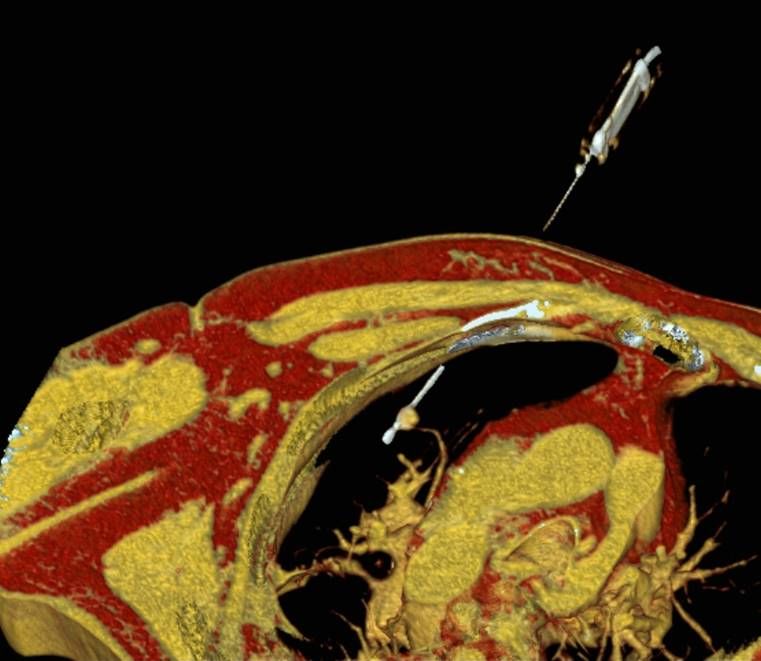

Abbildung: Bei der perkutanen Thermoablation von Lungentumoren werden spezielle Applikatoren unter CT-Bildgebung in den Zieltumor eingebracht. Durch Hitze wird der Tumor dann zerstört.